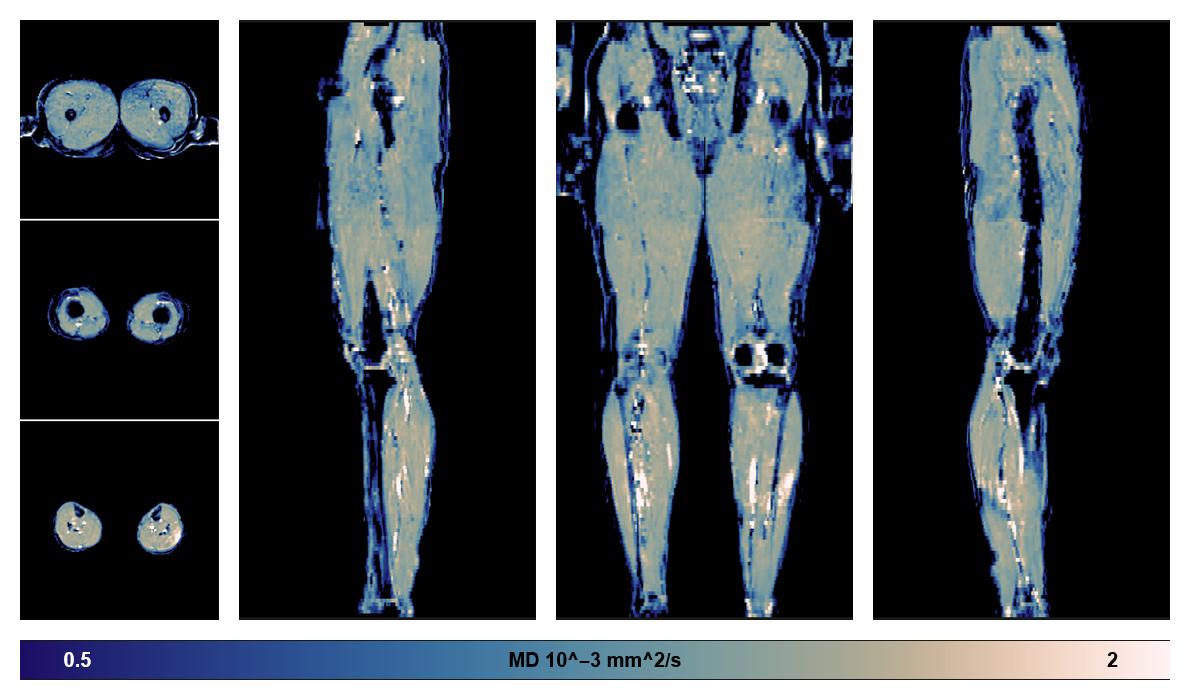

• Mean diffusivity

IVIM corrected whole leg muscle mean diffusivity obtained from diffusion tensor imaging.